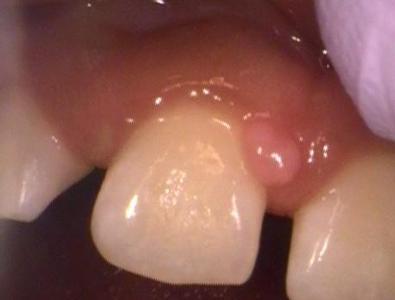

This patient had a benign lesion in between two of their teeth. We were able to remove the lesion via laser dentistry. The patient had fully healed gums after one week!

A piece of gum that has a lesion on it | laser dentistry vienna va patients mouth after a gum lesion has been removed | laser dentist vienna va